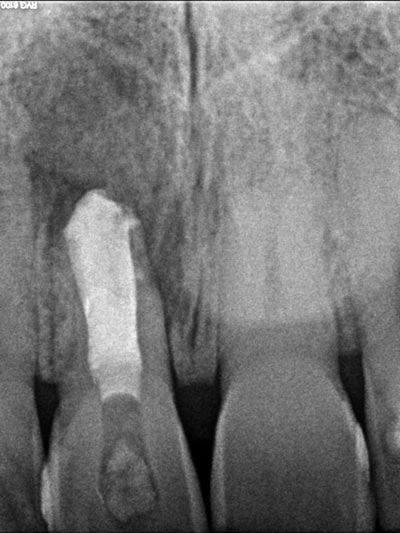

Imágenes: Endodoncia en un incisivo inferior calcificado y necrótico.